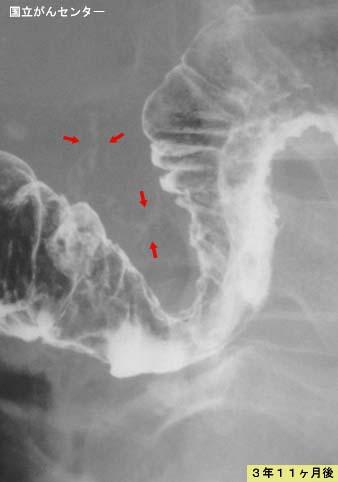

병변의 진행을 시간경과적으로 추적할 수 있었던 정맥경화성 대장염

염증성 및 궤양성질환/정맥경화성 대장염

대장/2구역 이상의 대장에 걸치는 것

X-P